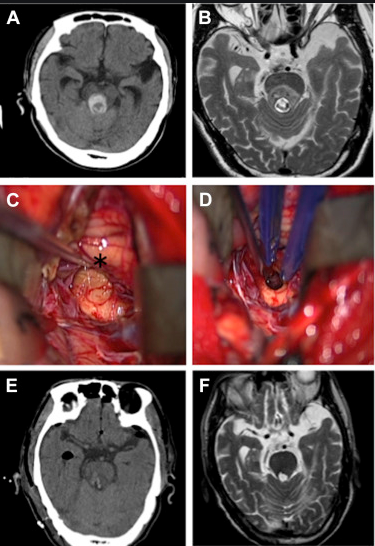

那么如何提高脑干海绵状血管瘤生存期呢?前面也说了,想要提高生存期,拥有一个长的生命,及时治疗是需的。而对于脑干海绵状血管瘤的治疗手术是主要手段,其中手术切除率的高低主要决定了治疗效果,理想状态下是全切,这样才能确定不复发。目前手术主要包括传统手术和显微外科手术,但传统手术切除率往往不能达到很理想的状态,因为凭借肉眼观察,很多时候往往并不能清楚的看清肿瘤所在,达不到一个理想的切除率。而显微外科手术借助于手术显微镜的放大,再结合神经导航、术中MRI、术中超声等辅助设备,视野更清晰、入路丰富,细致的显微手术器械及缝合材料,让血管瘤切除率达到更高,手术顺利性更有保障,创伤面积更小,并且患者生存率都有所提高。

海绵状血管瘤一般位置都不会固定的出现在同一个地方,每个人的脑海绵状血管瘤位置都会有所差异。以往的手术治疗入路单一,创伤面积大,而国际肿瘤颅底手术教授巴特朗菲教授拥有20年的脑干海绵状血管瘤的外科治疗经验,可以从多种入路更好的靠近多区域的肿瘤进行切除,减少患者术后的痛苦,减低感染的风险。术后,37%的患者表现出短暂的(轻微)神经功能缺损,其余超过90%的患者,神经功能与术前持平或好转。

在巴特朗菲教授一份关于72名海绵状血管瘤患者研究报告中显示,在显微外科手术后的72人中,大部分患者没有再出血等其他不良症状,术后生活质量得以明显好转。

参考文献:Tsuji Y, Kar S, Bertalanffy H. Microsurgical Management of Midbrain Cavernous Malformations: Predictors of Outcome and Lesion Classification in 72 Patients[J]. Operative Neurosurgery, 2019.